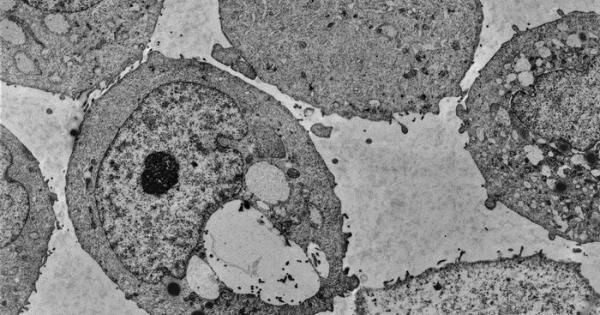

Учени от университета на Вирджиния САЩ съвместно със сътрудници от

...... че изследванията ни ще положат основите за откриването на нови маркери за проследяване на спящите ракови клетки", пишат авторите в публикация в сп. "Нейчър къмюникейшънс".